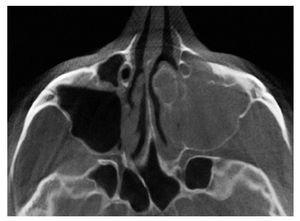

Figura 3. Tomografía volumétrica digital dental: plano axial.

En la TVD se observa un seno maxilar izquierdo íntegro y homogéneamente ocupado, además de una obstrucción del ostium fisiológico en ambos lados. Se aprecia también una opacificación subtotal de todo el complejo etmoidal y también del seno frontal. Estos hallazgos sugieren un diagnóstico de mucocele del seno maxilar izquierdo y de pansinusitis de los senos paranasales. En el lado izquierdo, en la zona de las celdas etmoidales superiores se observa una masa circunscrita de densidad similar a los tejidos duros junto con una obstrucción parcial de las celdas etomoidales izquierdas. Se trata probablemente de un osteoma.